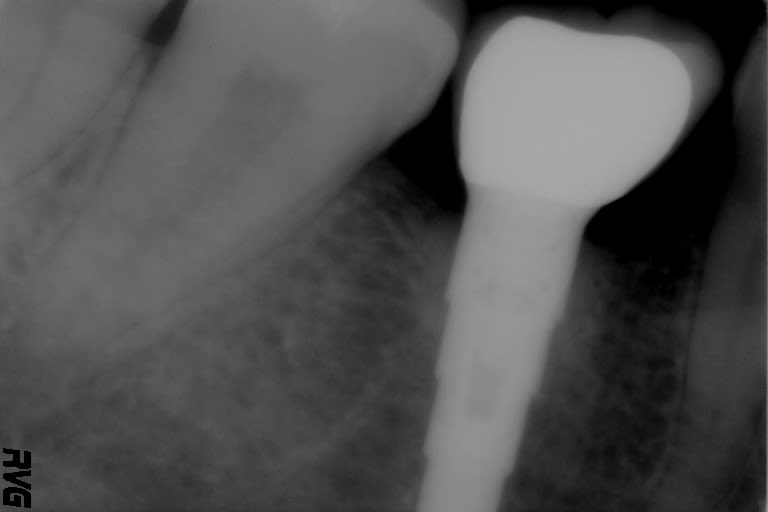

Bonjour, pour les connaisseurs, pouvez vous m'aider à identifier cet implant en 46 ?

Je pense à un frialit 2.

c'est un Frialit impacté.

+1 Frialit impacté